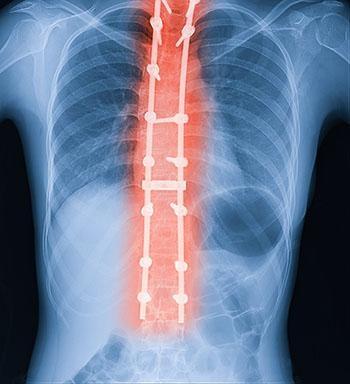

Edward went through a corrective spinal surgery in Nov. 2002 when he was 14 years old. That treatment aimed to correct the curvature as far as possible and then fuse the vertebrae together to prevent further curvature. Surgical hardware, such as metal rods, screws, and hooks, is also used during the procedure to ease the bone around the devices.

According to the medical malpractice lawsuit, the surgeons had misplaced four screws in Edward’s spine, which compressed his spinal cord. It caused nerve damage, paralyzing Edward from the waist down. Despite this handicap, Edward went to college. He also took a job repairing computers, but his parents maintained that his overall functionality was minimal. He also never played hockey (his favorite sport) again.